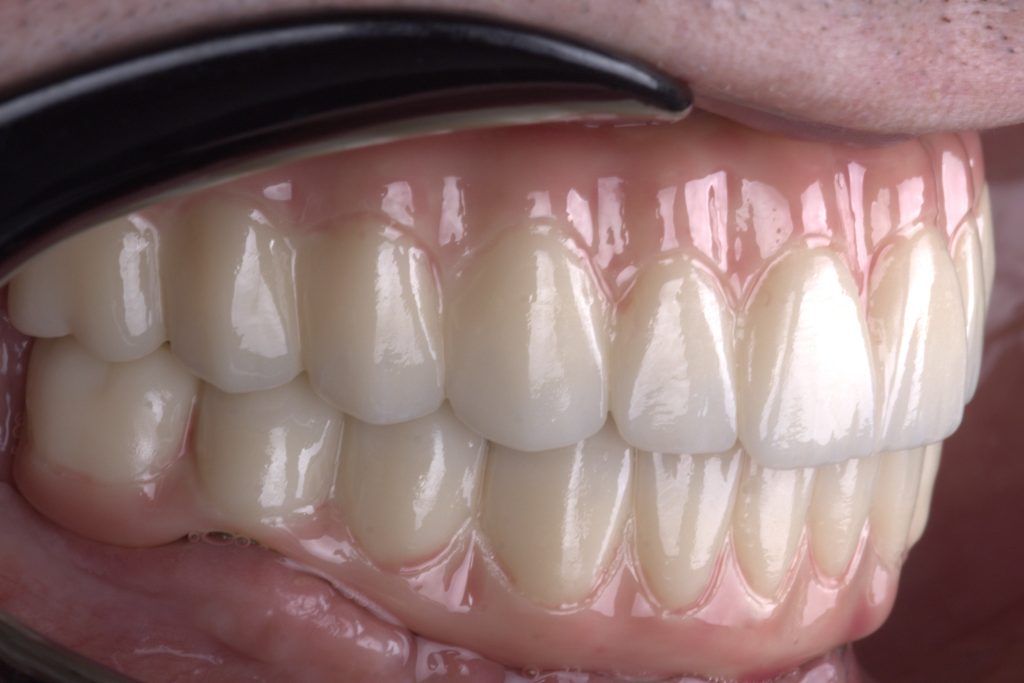

The beauty of precision: Capturing the perfect bite in monolithic zirconia.

Exceptional monolithic zirconia expertly crafted by our laboratory team at White Clinic Belgrade

Visual satisfaction: The seamless occlusion of monolithic zirconia at White Clinic Belgrade.

The beauty of precision Capturing the perfect bite in full contour zirconia